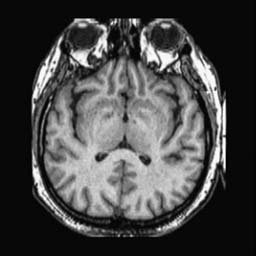

To demonstrate the effectiveness and efficiency of the proposed image fusion method , we conduct a set of comparative experiments on three image datasets. The first is composed by 8 pairs of multi-modal medical images and the second one contains 15 pairs of multi-focus gray or color natural images. These two datasets are often used in many related papers and some examples are shown in Figure 3(a) and Figure 3(b). The third one is a new multi-focus cervical cell image dataset collected by ourselves, which consists of 15 groups of color images and each group contains a series of multi-focus cervix cell images with size of or , etc. Some source examples are shown in Figure 3(c). Our source code implemented in C++ along with the new multi-focus cervical cell image dataset is available online.

We first evaluate the performance of the proposed method under varying total number of octaves and number of layers sampled per octave. The fused images of a pair of multi-modal medical images with different and are shown in Figure 4. In this example, on the one hand, when only 1 or 2 octaves are involved in constructing the DoG pyramid, the fused images fail to keep the integrity information of large size objects (e.g. eyeballs), while by increasing the value of , the integrity information of eyeballs is preserved. On the other hand, although not as significant as the increase of octave numbers , the fused image can contain more details by the increase of layer numbers . The corresponding objective quality metrics are shown in Figure 5. As shown in Figure 5(a), most of the metric values are improved as the number of octaves increases with the fixed layer numbers 3 in the global tendency and each of them tends to be stable when the number of octaves is 5. To get a relatively good quality from Figure 5(b), we can notice that some of the metric values can get a good performance when the number of layers is 3, such as the MI, SSIM, QI and VIF, though there are only a little change of all the metric values by increasing the number of layers with the fixed octave numbers 5. Because it will result in more computation burden with the increase of the value and , and for different kinds of source images, there are different performance with the diverse parameter settings. To get a trade-off between them in our experiments, we set for the multi-modal dataset, for the natural datasets and for the multi-focus cell dataset, respectively.

Figure 6 shows the fused images obtained by different methods with the multi-modal source images shown in Figure 3(a). As shown in these figures, the proposed method can produce images which preserve the complementary information of different source images well. Moreover, due to the scale-invariant structure saliency selection, our method can keep the integrity information of large size objects and the visual details simultaneously. Although the fused image generated by other methods can also capture the details to some extent, all of them fail to keep the integrity information of large size objects such as the eyeballs. Furthermore, from Figure 6(k)-6(t), the DTCWT, GFF, IM and NSCT methods may decrease the brightness and contrast while the proposed method can preserve these features and details without producing visible artifacts and brightness distortions.